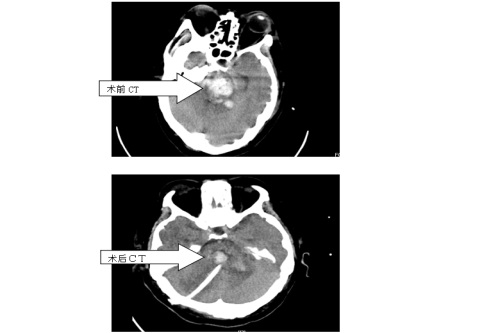

近日,临床医学院/附属医院神经外科成功为一例脑干出血患者行九江地区自主进行的首例“立体定向下脑干出血穿刺外引流术”,手术顺利,置管成功,术后引流效果佳。

患者入院时呈神志深昏迷状态,GCS4分,CT提示脑干出血。脑干出血是脑出血中最凶险的一种,一直被认为是手术禁区,患者死亡率及致残率极高,以前传统治疗均为给予药物保守治疗。近年来有些大医院开展开颅手术清除血肿,但并不能改善患者预后,没有得到广泛推广。经过与患者家属充分沟通,神经外科赵浪平主任医师带领张国斌副主任医师,周嘉敏、黄启伟主治医师,朱鹏博医师等一起为患者行“脑干出血立体定向下穿刺外引流术”。该手术具有恢复快、住院时间短、治疗费用低等优点,是一种创伤小、治疗确切、家属容易接受的治疗手段。